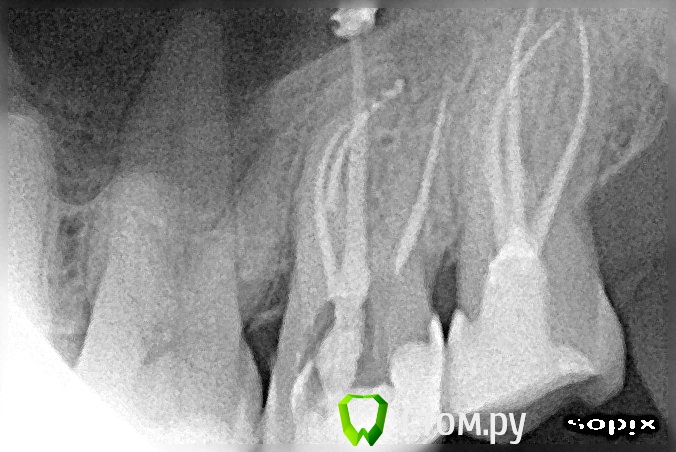

Miria Опубликовано 26 мая, 2014 Поделиться Опубликовано 26 мая, 2014 Здравствуйте!В начале марта 2014 г. лечила 28 (периодонтит острый серозный, зуб болел с декабря 2013 г.) под анестезией, лекарство и временная пломба на 1-м приеме, пломбировка 3-х каналов термафил и постоянная пломба на 2-м приеме (через 8 дней). После лечения болей не было.1 апреля лечила 27 (пульпит хронический в стадии обострения фиброзный, зуб болел с декабря 2013 г.) под анестезией, пломбировка 4-х каналов термафил на 1-м приеме, постоянная пломба на 2-м приеме (через 9 дней). После лечения зуб болел 4 дня, сразу появилось: тепло в области левых скулы и виска; распирание всего зуба, которое усилилось далее; подергивание нерва глубоко в левой щеке ближе к носу. Через 10 дней началось онемение в области левых скулы и глаза, позднее резко ухудшалось зрение. Зуб был болезненный при задевании, ломота, неприятный вкус слюны около 27.25 апреля был распломбирован один канал (небный) и пройден до верхушки, оставлено лекарство, временная пломба (по плану на 24 дня). Прошло онемение скулы и глаза, восстановилось зрение. Распирание, ломота, болезненность, тепло в виске и скуле, подергивание нерва в щеке продолжались и случился сильный приступ боли через 7 дней.3 мая снята временная пломба, лекарство, временная пломба. Пропила назначенный Рулид 5 дней по 1 таблетке 2 раза в день. Исчез неприятный вкус слюны. Распирание, ломота, болезненность, тепло в виске и скуле, подергивание нерва в щеке продолжались.7 мая снята временная пломба, частично распломбирован еще один канал (который по снимку ближе к 26), лекарство, временная пломба. Подергивание нерва в щеке и тепло немного уменьшились. Распирание, ломота, болезненность продолжались.19 мая (24-й день после распломбировки небного канала) снята временная пломба, немного распломбирован еще один канал (который по снимку ближе к 28), запломбирован небный канал, временная пломба.Распирание, ломота, болезненность при задевании, покалывание в щеке, постоянное подергивание нерва в щеке (ближе к носу) продолжаются. Не совсем прошла боль в виске. На снимке выведена пломбировка за апекс.Очень переживаю за зуб. Вопросов много и срочные, может, что еще скажете.1. Почему может болеть зуб 27?2. Какова методика дальнейшего лечения 27?3. Нужно ли убирать выведенный материал, если он дает такую реакцию? Или со временем боль может пройти (такая боль продолжается с первого приема лечения с 01.04.2014, терпению давно предел)?4. Может ли получиться убрать выведенный материал за верхушками через распломбированные каналы или как? (По-моему хирургически просто не добраться) И если вновь распломбировывать – то распломбировывать надо сразу все каналы (небный канал запломбирован два раза)?5. Повторное эндодонтическое лечение намного хуже для зуба или как оно влияет на дальнейшее функционирование зуба?Спасибо огромное за Ваши время и ответ, который очень жду! 1 Ссылка на комментарий

Miria Опубликовано 12 июня, 2014 Автор Поделиться Опубликовано 12 июня, 2014 Здравствуйте, добавляю снимки. Ссылка на комментарий